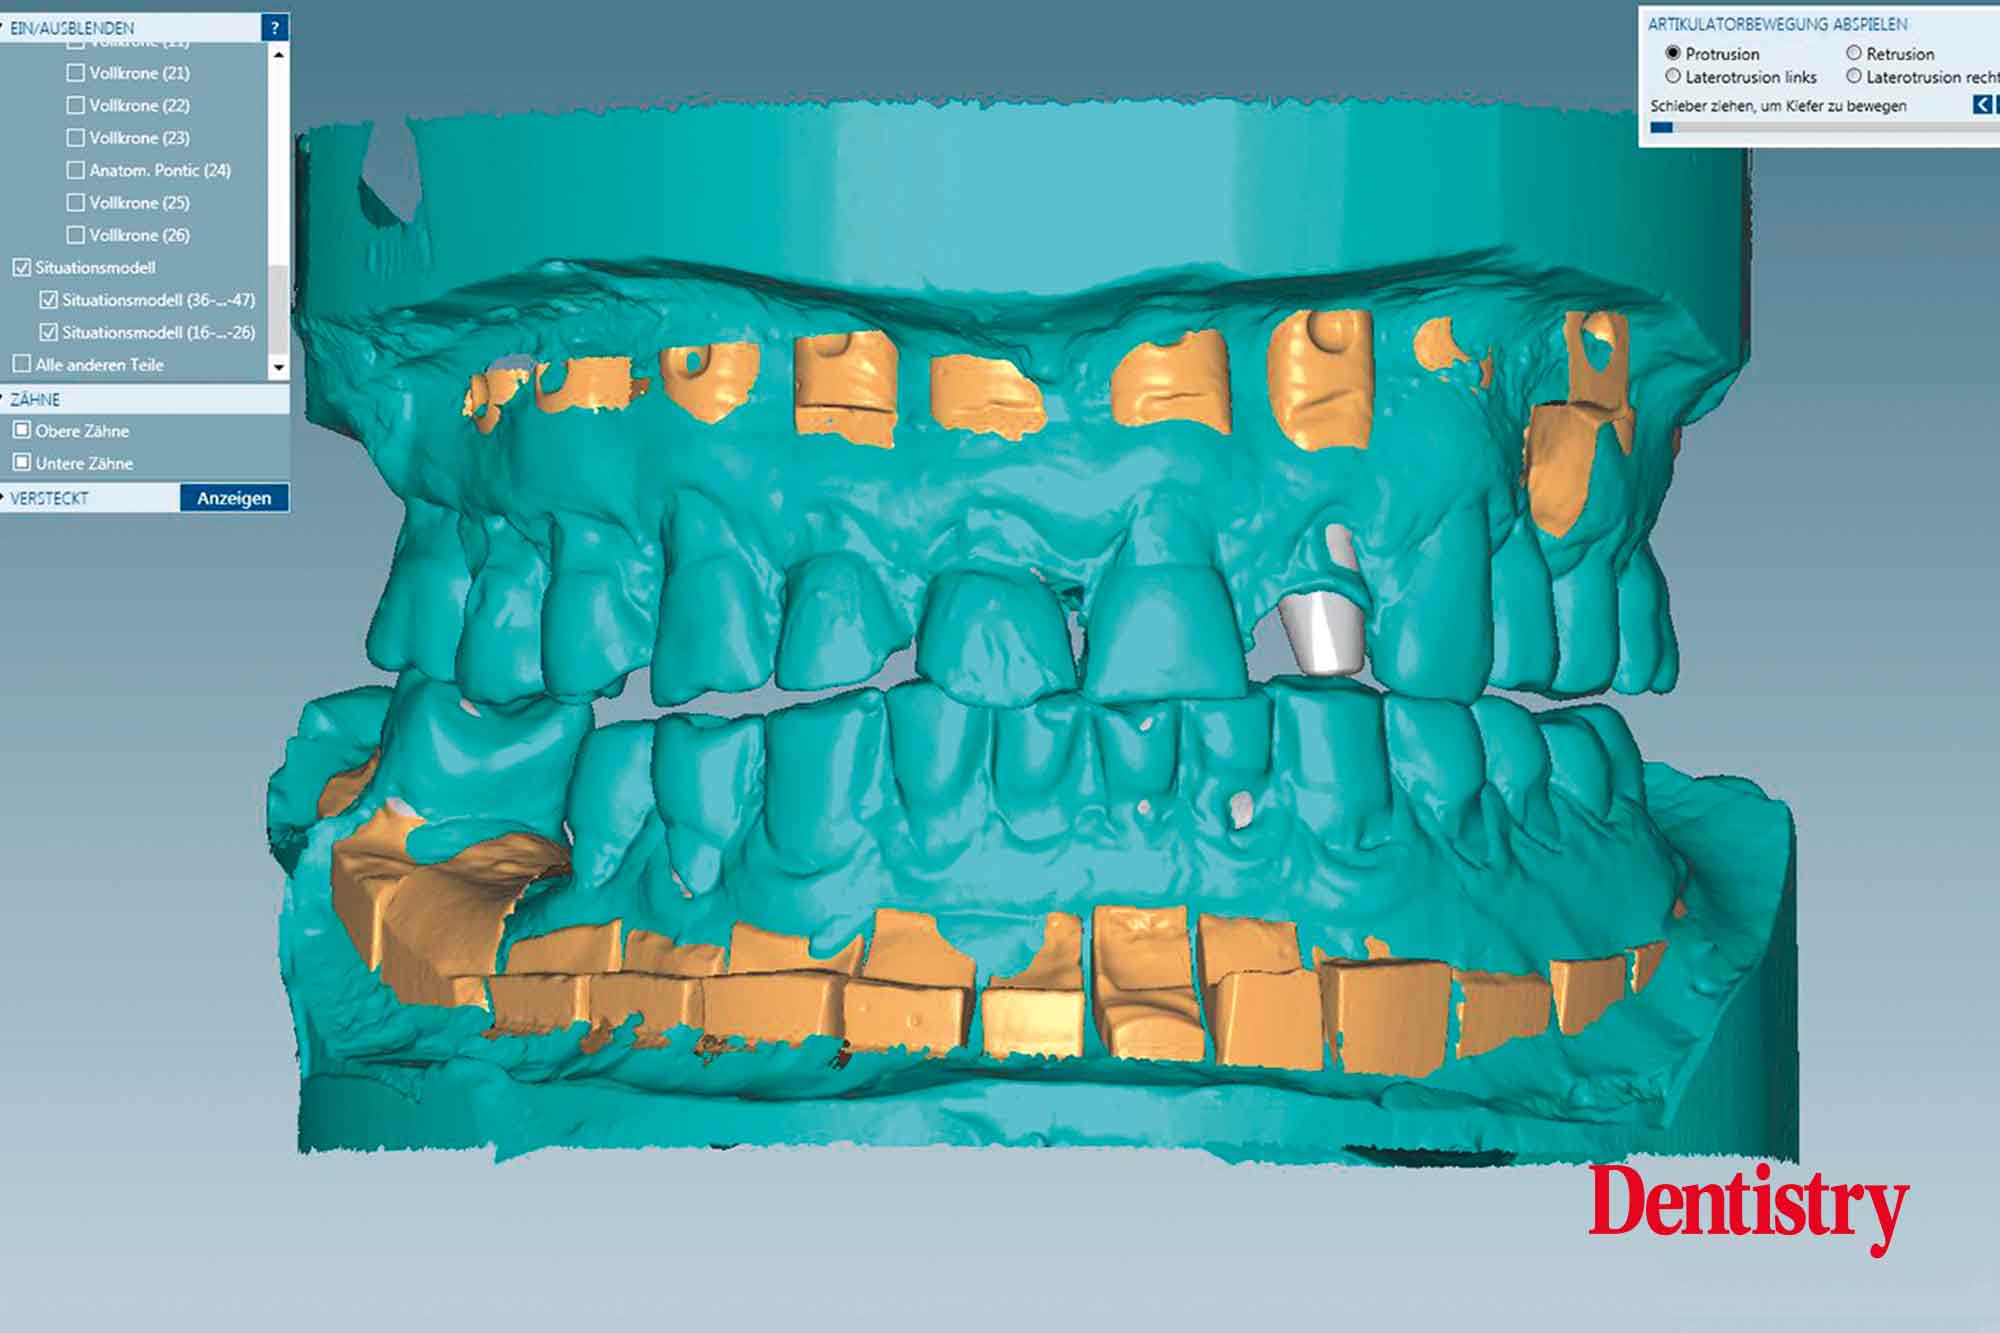

The scanned models were evaluated on a virtual 11 articulator. Temporary Ceramill PMMA (Amann Girrbach) transparent acrylic crowns were CAD planned (Figures 3a to 3d).

Patient data including condylar movements were recorded by the software. Using the Initial situation software’s customised incisal guide unit, the incisal guide pin was adjusted on the splitex plate to the desired cuspal inclinations on the virtual temporary crowns (Figure 4).

All patient parameters including condylar inclination were transferred to the Ceramill Artex articulator and the lateral and protrusive excursions were established while having no contact with the anterior teeth (Figures 5 to 8).